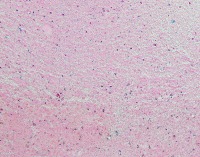

Medical Diagnostics: geckler5 can be used in healthcare facilities to analyze images of tissue samples, blood smear slides, or other medical images to detect the presence and distribution of White Blood Cells (WBC) and Erythrocyte Hemoglobin Concentration (EHC). This can aid in diagnosing diseases such as infections, anemia, or leukemia.

Research and Development: Scientists working in the field of hematology or immunology can use geckler5 to analyze large datasets of blood samples in their research studies. This can help them better understand blood cell morphology, variations, and concentrations in different conditions, ultimately leading to new medical discoveries.

Pharmaceutical Testing: The pharmaceutical industry can utilize geckler5 to analyze the effects of new drugs or treatment methods on WBC and EHC levels. This would allow researchers to monitor the efficacy, side effects, and other critical factors for drug trials and approval processes.

Educational Purposes: Educational institutions teaching medical or biological courses can implement geckler5 as a learning tool, helping students to identify and differentiate between various blood components. This can enhance their understanding of blood cell compositions and related medical conditions.

Blood Donation Centers and Blood Banks: geckler5 can be employed to assess the quality of blood donations in terms of WBC and EHC levels. This automated analysis would help staff ensure that donated blood meets necessary standards and is safe for transfusion into patients.